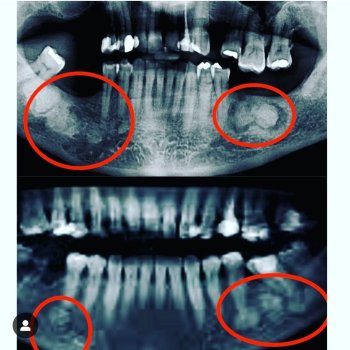

Normalmente, eles não se desenvolvem na dentição decídua, ou seja, não se manifestam nos dentes de leite da criança, aparecendo apenas com a formação da arcada permanente. Isso significa que sua formação ocorre entre os 6 ou 7 anos de idade. Na maioria dos casos, os dentes afetados são os incisivos centrais (dentes anteriores) e os molares (dentes posteriores). Os incisivos se desenvolvem em formato que lembra uma chave de fenda. Os dentes molares também podem apresentar um formato diferenciado, contando com um formato que lembra uma amora, com várias protuberâncias irregulares.

Além disso, outra característica dos dentes de Hutchinson é o maior espaçamento entre os dentes e a presença de sulcos em seu interior.